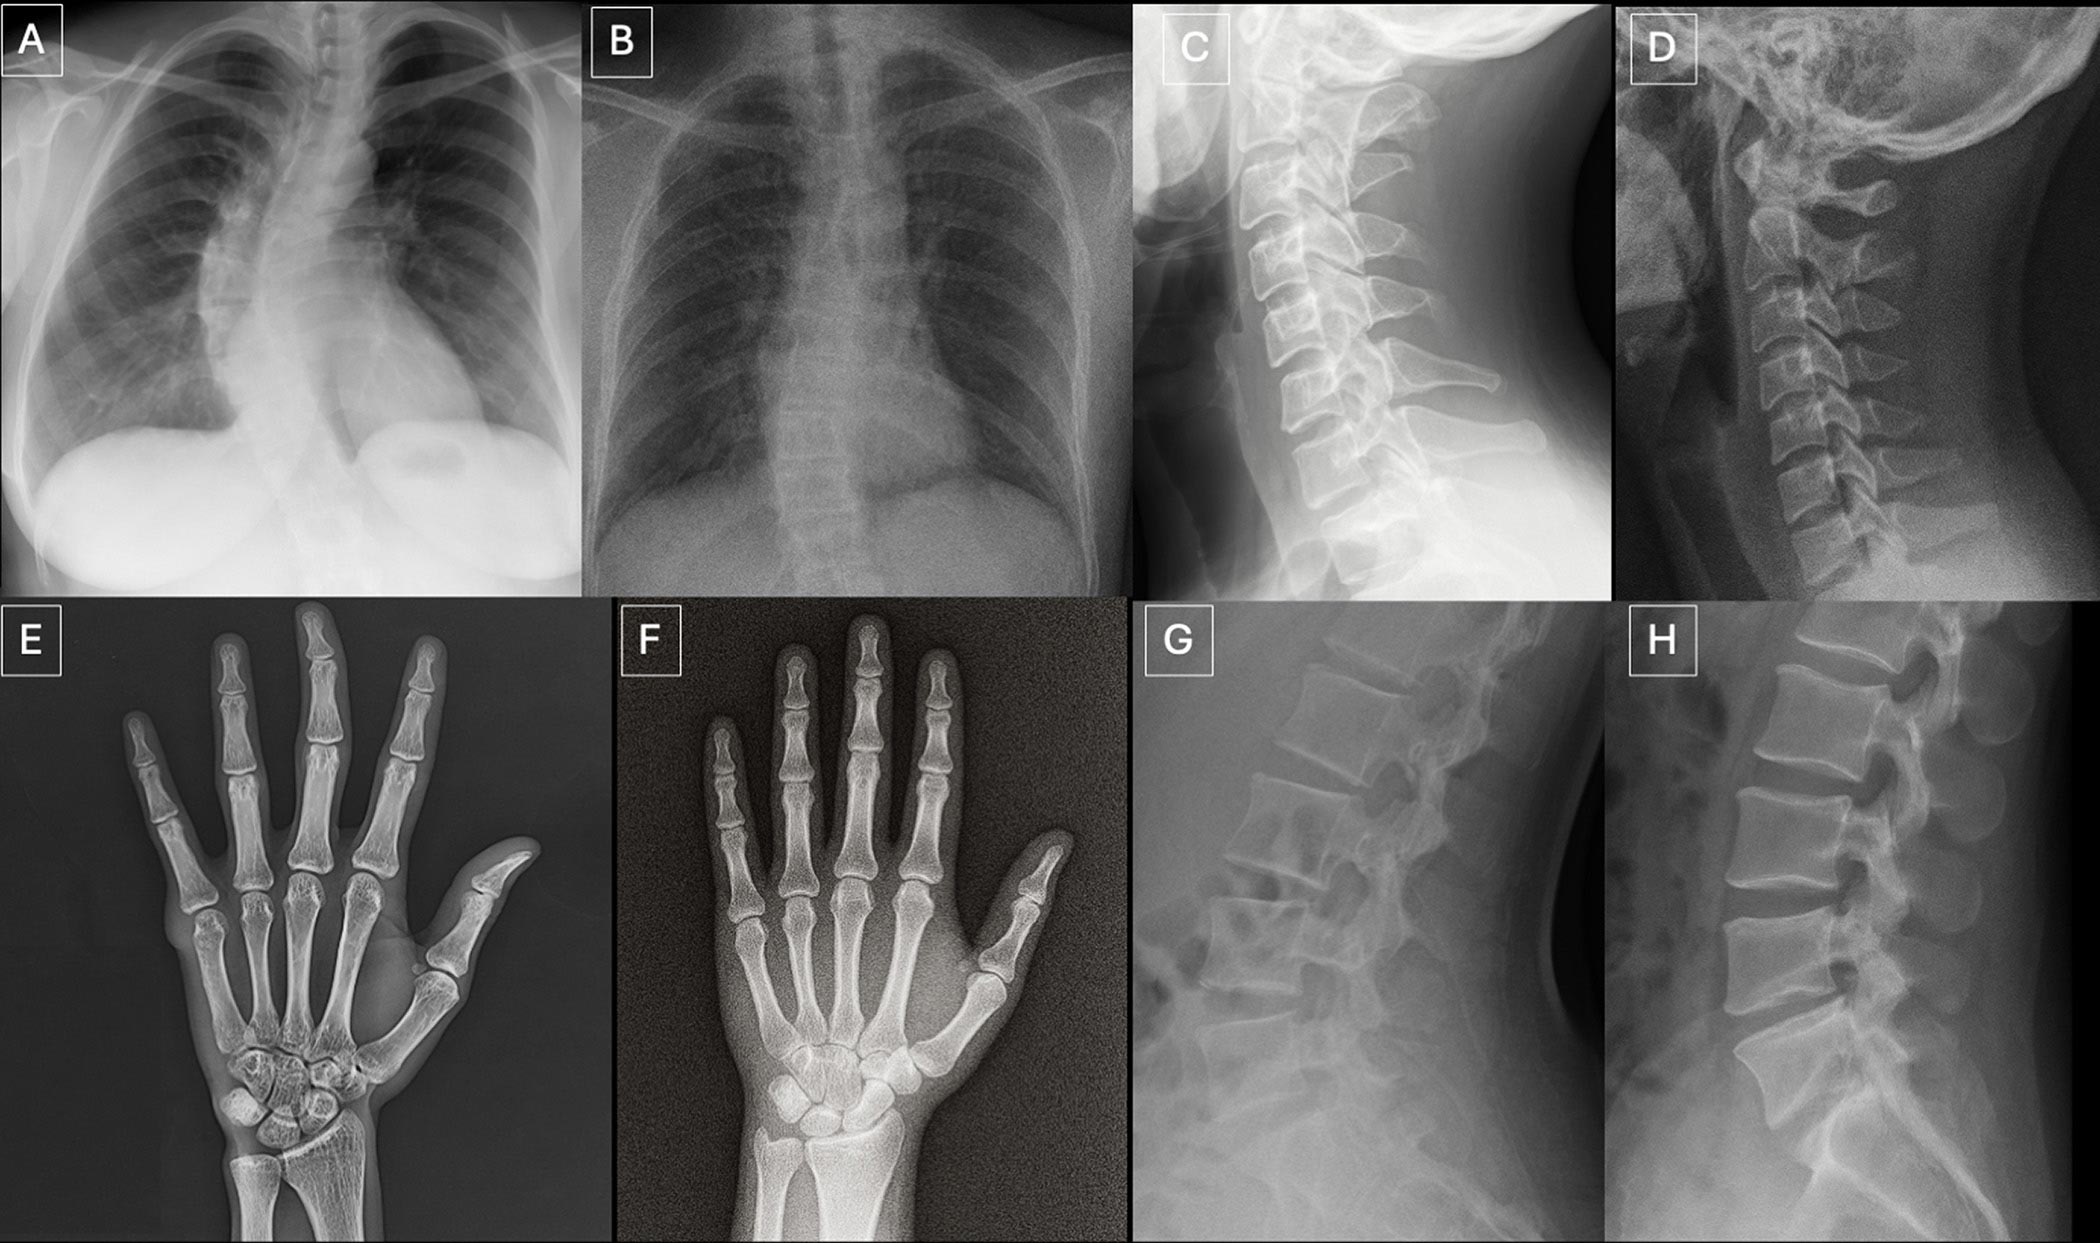

A multi-center study found that radiologists and advanced AI models cannot reliably distinguish AI-generated deepfake X-ray images from authentic ones. This vulnerability exposes healthcare to risks such as misdiagnosis, fraudulent litigation, and cybersecurity threats, highlighting the urgent need for improved detection tools and training.[AI generated]